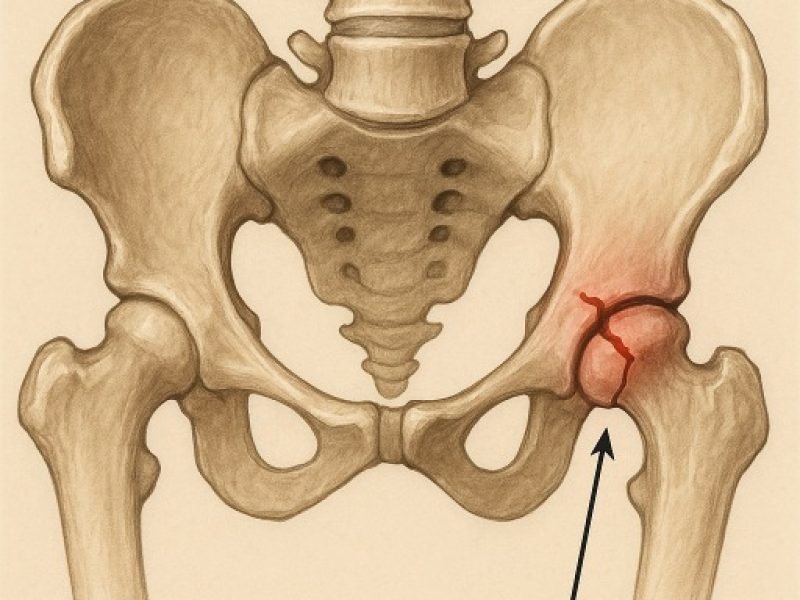

We provide specialized surgical care for pelvic injuries, using precise techniques to stabilize the pelvic structure and promote a safe, complete recovery.